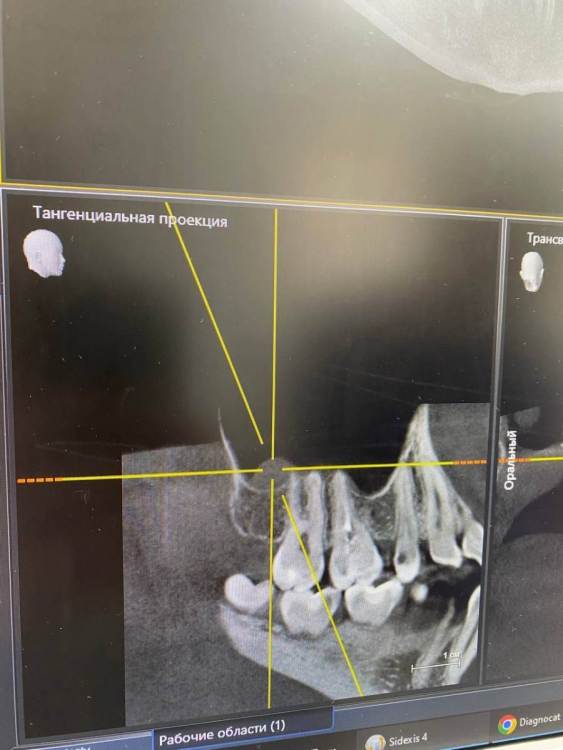

Здравствуйте. В начале марта я сходила на прием, была пролечена (депульпированна) верхняя правая шестерка. После установки временной пломбы в течение двух недель не прекращались ноющие ощущения, поэтому было решено с врачом перелечить зуб. Зуб перелечили, но ноющие боли по-прежнему остались. Зуб не реагирует на холодное/горячее, не шатается, однако реагирует на постукивания.

Была у лора, в одной пазухе есть полип. Может ли он влиять на зуб? Также была у окулиста и невролога с целью исключения патологии тройничного нерва. С этим все в порядке.

Два дня назад треснула эмаль зуба и врач хочет поставить все-таки временную коронку. Я пока сомневаюсь и честно говоря не знаю, что делать, потому что эти странные ноющие ощущения в зубе по-прежнему актуальны. Да и как ставить коронку на зуб, который болит от того, что по нему стучат?...

Была уже у трех врачей, но все говорят, что зуб запломбирован нормально и четкого ответа никто дать не может.

Буду благодарна за любую помощь и ответ. photo_2023-08-09_18-14-31.thumb.jpg.e23f86db67c6866262d362dc6a8b8242.jpgphoto_2023-08-09_18-14-29.thumb.jpg.b2e19e72b9027bf4e4a44185f0ca97e4.jpgphoto_2023-08-09_18-14-25.thumb.jpg.afbef81bf80ad897dc7ffd28efc2453a.jpg

photo_2023-08-09_18-14-28.jpg